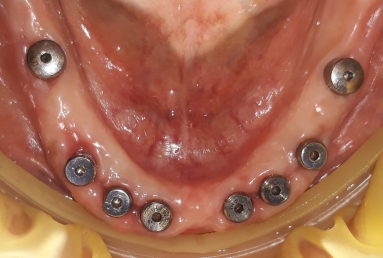

Our patient suffered from advanced periodontitis and we had to extract all mandibular teeth. After 2 month we inserted 8 Alpha Bio implants that healed in 4 months. All this time a full mobile temporary prosthesis was made, that was replaced in the end with fixed restorations made of porcelain fused to metal.